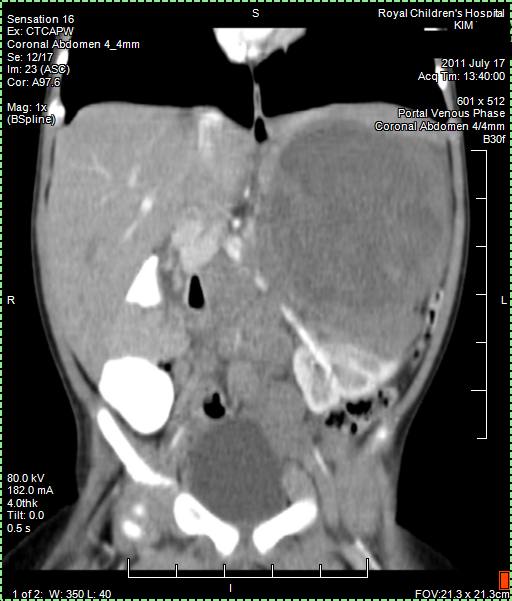

Today we got the Radiology Report back of the 25 August CT (CAT) scan. Papa still has a few remaining questions about it but it confirmed that the tumour shrank as papa thought to see himself from the images. Good news!

Papa collected copy of CT (CAT) scan images from Radiology. Looking at them it seems that the main tumour shrank from around 11 cm to 6 cm and there is less evidence of Nodes. But we have to await Radiology Report to be sure about this positive news. Lets hope Papa is right.

17 July 2011, Sunday

CT (CAT scan) abdomen under anaesthetic, confirms cancer. We await the Radiology Report. There is no way knowing what kind of cancer, but it is suspected maybe Neuroblastoma. We learn that there are different types of Neuroblastoma some of which are low risk and can easily be treated or removed. It is very worrying not knowing more.